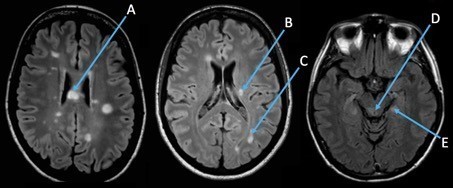

Question 12 : Parmi les lésions présentes sur son IRM cérébrale en séquence FLAIR, quelle est celle responsable de la diplopie survenue il y a un an et demi ?

L’ophtalmoplégie internucléaire droite est liée à une atteinte du faisceau longitudinal médian droit dans le tronc cérébral et correspond donc à la lésion D.

La lésion A correspond à une lésion située dans le corps calleux qui est le plus souvent asymptomatique mais peut donner des syndromes de déconnexions du corps calleux.

La lésion B est une lésion périventriculaire.

La lésion C est une lésion juxta-corticale occipitale qui peut être responsable d’une hémianopsie latérale homonyme droite.

La lésion E est une lésion juxta-corticale temporale interne qui peut entrainer des troubles de la mémoire.